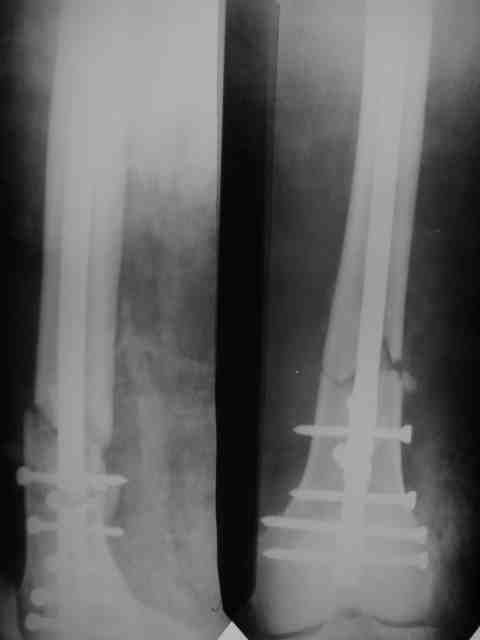

Глубокоуваемый Игороь Садовник, зачем так нагнетать страсти? Проблема состоит в оснащенности клиник, а не в том, чьего производства фиксатор. У нас в клинике тоже отсутсвует ЭОП. Поэтому чаще пользуемся импортными канюлированными конструкциями, и завидуем тем у кого есть отечественные винты 6 мм из-за возможности ранней послеоперационной нагрузки. Бедро/голень/плечо занимают 1.5-2 часа, если сплошной гвоздь время операции на бедре удваевается, на плече/голени практически нет. Открываемся редко в тяжелых несвежих случаях. Дистальное блокирование с направителем, промахи были в первых нескольких случаях,когда больного снимали со стола, сейчас без блокирования штифт не остается. Основаное время операции занимает попадание проводником в дистальный от точки взода отломок + Рг.

Попутно, разрешите поделится опытом закрытого ретроградного синтеза бедра. Внедрение тяжелая штука, пости года 2 прошло со времени обучения методике. Использовать/убедить использовать дистрактор на бедре/голени удавалось редко. Отлично дистрактор прижился на плече. Зав. отделением не знал точного плана операции(поэтому не смог помешать).Стокнулись со следующей проблемой - при попытке устранить ротацию теряли длину, при дистракиции получали ротацию, при чем при ротации телескопы очень плотно давят на бедро. Больная с ожирением, на ощупь проводили спицу проксимальной опоры, пульсацию бедренной артерии для ориентира определить не возможно. Проксимально латеральный телескоп все время оказывался длиннее, чем надо, меняли его положение.Не смотря на все это, считаю, без дистрактора данная операция заркрыто не возможна , особенно в наших условиях.

Успешный опыт пользвания дистрактором есть(я сам видел, не видел бы- бросил бы попытки пользования дистрактором). Пожалуйста, укажите на допущенные ошибки. Спасибо.

Рг в приложении.

КАН> допущенные ошибки. Спасибо. Рг в приложении.

Снимки вполне симпатичные. Единственное, по ротации не понял, уж больно неразборчивый тот, который без гвоздя.